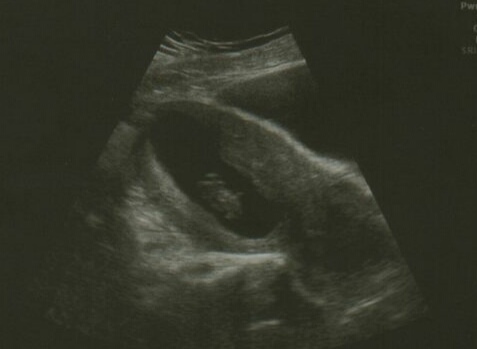

Had a private scan today. Obviously it's behind many of yours, because I'm not quite 10 weeks yet, but glad I did it (£40).

It was doing some crazy womb dancing, but perfect size and heartbeat for its age.